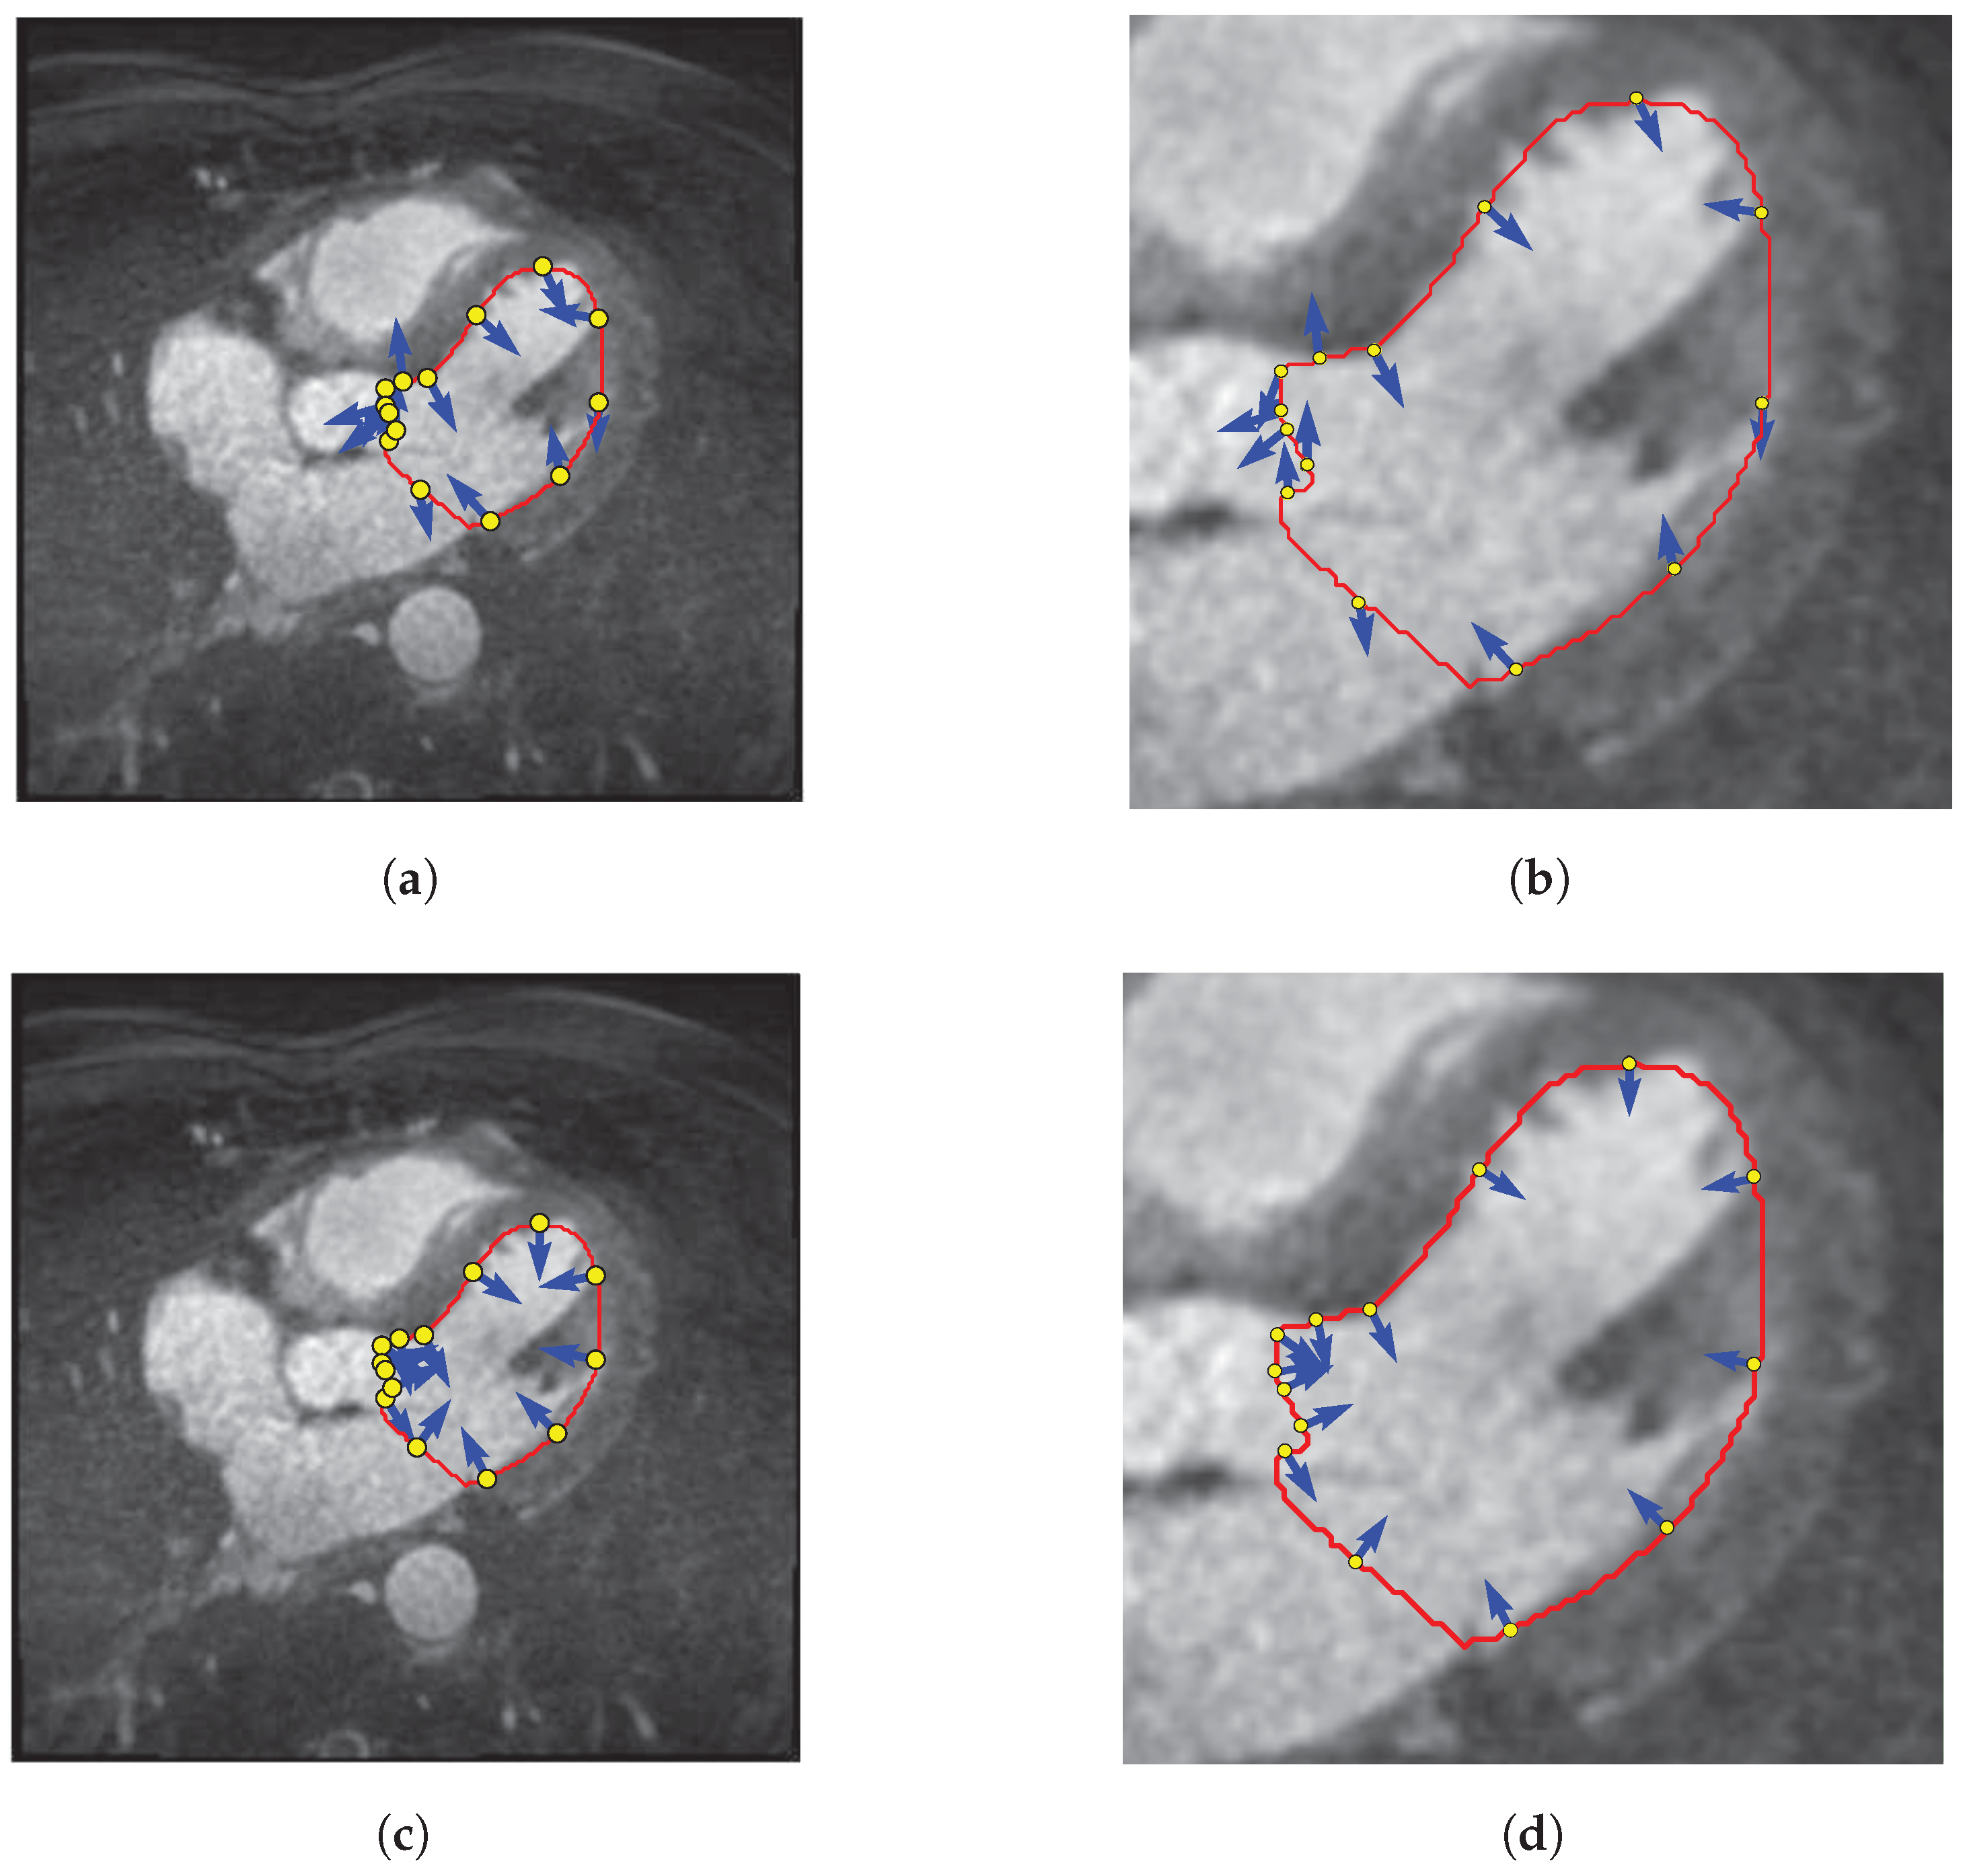

2.2. Control Point Extraction

2.3. Control Point Merging

2.3.1. Contour Intersection

2.3.2. Classification and Merging